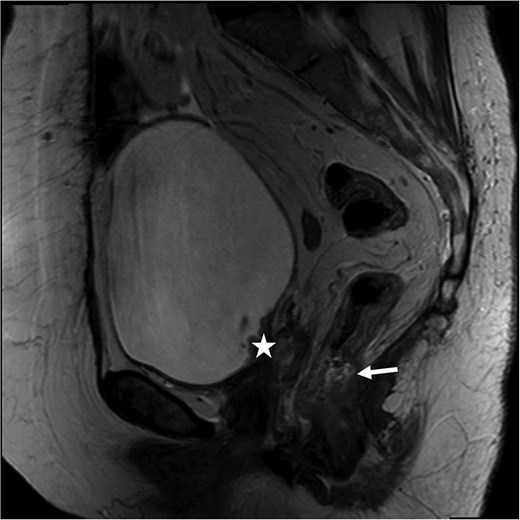

At her next colonoscopy, a palpable posterior rectal mass was biopsied confirming rectal adenocarcinoma with positive caudal type homeobox 2 (CDX-2) and negative paired box gene 8 (PAX-8). The tumor was mismatch repair (MMR) proficient and microsatellite stable. Imaging showed progression of the vaginal cuff mass extending to the bladder with right hydronephrosis. Magnetic resonance imaging (MRI) indicated a cT3 cN0 rectal tumor separate from the vaginal recurrence (Fig. 1). Cystoscopy revealed a tumor in the right hemitrigone, biopsy confirmed urothelial carcinoma.

Rectal MRI, sagittal view. Star marks vaginal cuff mass with bladder invasion; arrow marks rectal tumor.